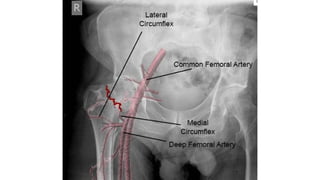

This document discusses femoral fractures, categorized by their location and severity, with classifications such as Garden classification. It outlines the types of fractures, including valgus impacted, non-displaced, partially displaced, and fully displaced, along with their surgical treatment options. Additionally, it briefly describes distal femur fractures, which occur just above the knee joint.